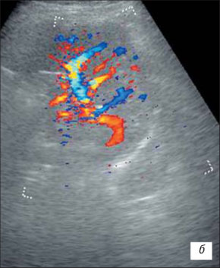

УЗІ нирки при запальних змінах в режимі ЦДК

а – інтраренальний судинний малюнок нирки збережений, кортикальный кровотік визначається у всіх відділах паренхіми;

б – збіднення судинного малюнка;

в – швидкісні показники в гирлі ниркової артерії в межах вікової норми: Vps – 83,7 см/с; Ved – 34,1 см/с; RI – 0,63; PI – 0,96.

На розгорненій картині УЗІ з ЦДК характеризується нерівністю, нечіткістю, деформацією контура нирки, який місцями може не простежуватися; нирка іноді місцями погано диференціюється від навколишніх тканин, що утрудняє визначення її розмірів; візуалізуються дрібні, неправильної форми втягнення контура, розподілені або по всьому контуру, або в якомусь фрагменті нирки; визначається нечіткість кортико-медуллярной диференціювання; є виражені дифузні зміни паренхіми нирки з помірним нерівномірним підвищенням її эхогенності; дилатація чашечно-мискової системи; фрагментарне стоншування паренхіми нирки з компенсаторним потовщенням або збереженням товщини інших її ділянок помірне збіднення інтраренального судинного малюнка, найбільш виражене в місцях деформації і втягнення контура нирки; зниження швидкісних характеристик артеріального кровотоку (мал. 3).